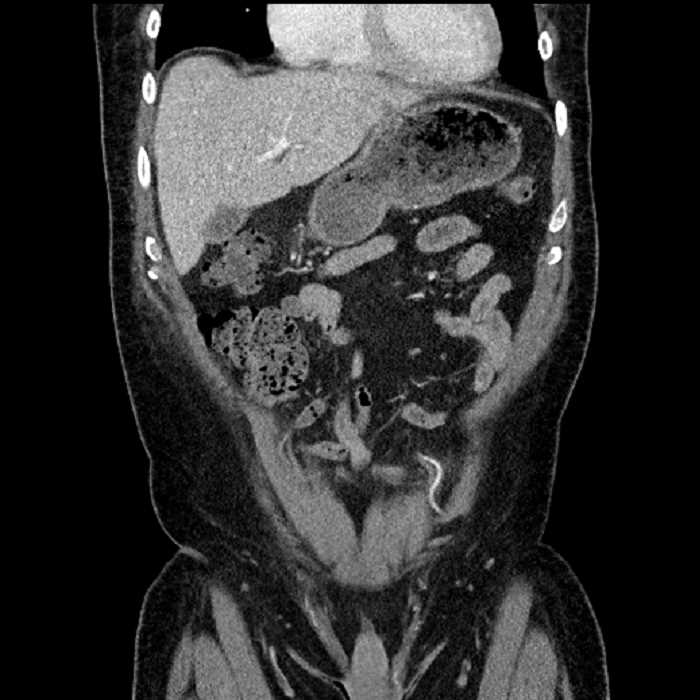

Age: 63

Sex: Male

Indication: Abdominal pain

• Large fluid density structure in hepatic segments 7 and 8 measuring 10 x 7 x 7 cm with internal septation and circumferential ill-defined low density compatible with edema

• Peripherally enhancing subcapsular collections along the anterior margin of the left hepatic lobe measuring 3 x 1 cm and 2 x 1 cm

• Clearly marginated fluid density structure in segment 7 and several other scattered tiny hypodensities, which likely represent cysts

• Hepatic abscess

Acute sigmoid diverticulitis complicated by a small contained perforation and a large abscess in the right hepatic lobe. Additional small subcapsular abscesses along the anterior margin of the left hepatic lobe.

• The classic CT imaging appearance is a double target sign with internal low density surrounded by an internal enhancing rim (capsule) and a low density external rim (edema)

• Abscesses may be unilocular or multilocular

• Gas is present in a minority of cases

Hepatic abscess showing the double target sign with low density internally surrounded by a thin inner enhancing rim (red arrow) and ill-defined outer low density rim (yellow arrow). Blue arrow indicates an internal septation. Red arrows: additional smaller subcapsular abscesses. Red arrow: focal contained perforation associated with diverticulitis.